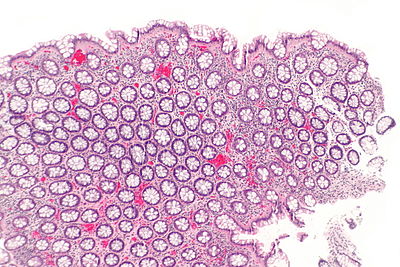

From Libre Pathology

Diagnosis?

Tubular adenoma - ase -- low mag.jpg

Adenocarcinoma

Colorectal mucosa within normal limits

Ganglioneuroma

Hyperplastic polyp

Inflammatory polyp

Juvenile polyp

Peutz-Jeghers polyp

Sessile serrated adenoma

Traditional serrated adenoma

Tubular adenoma

Tubulovillous adenoma

Villous adenoma

Xanthomatous polyp